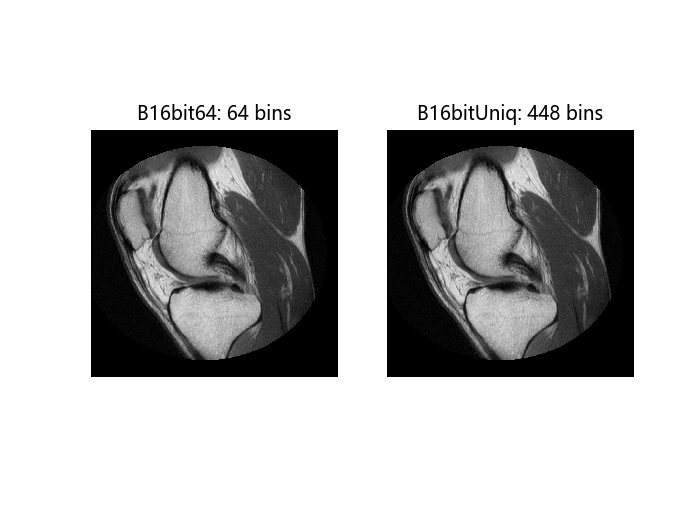

匹配 16 位灰度 MRI 图像的直方图

这个例子展示了如何使用不同数量的箱子进行直方图匹配。

使用不同数量的箱子生成直方图匹配的输出图像。首先使用默认的箱子数量 64,然后使用图像 A 中存在的值的数量,即 448 个箱子。

B16bit64, = imhistmatch(A[:,:,1],Ref[:,:,1]); # default: 64 bins

N = length(LevelsK); # number of unique 16-bit code values in image A.

B16bitUniq, = imhistmatch(A[:,:,1],Ref[:,:,1],N);

查看这两次直方图匹配操作的结果。

figure()

subplot(1,2,1)

imshow(B16bit64)

title("B16bit64: 64 bins")

subplot(1,2,2)

imshow(Ref)

title("B16bitUniq: $(N) bins")